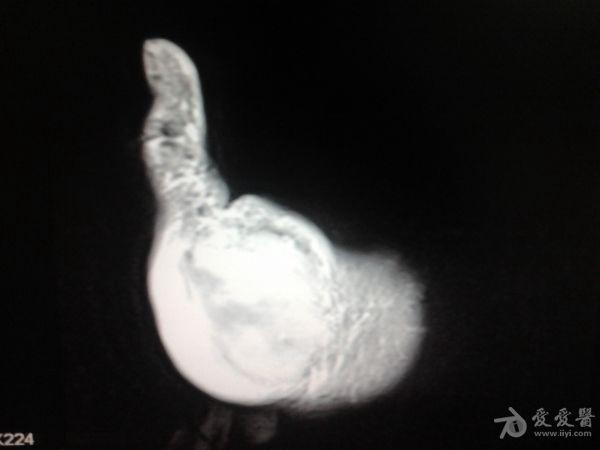

右第一掌骨、大多角骨肿瘤

男性患者,81岁,右手肿痛3个多月。无任何其它症状。体查:右手第一掌骨部肿胀明显,第一指活动受限,余四指活动可,腕关节活动小部分受限,活动时会痛。影像学检查如下。活检示:弥漫性大B细胞淋巴瘤。大家看看需不需要截肢?现在有人主张手术;有人主张不手术,直接化疗。大家有什么看法?